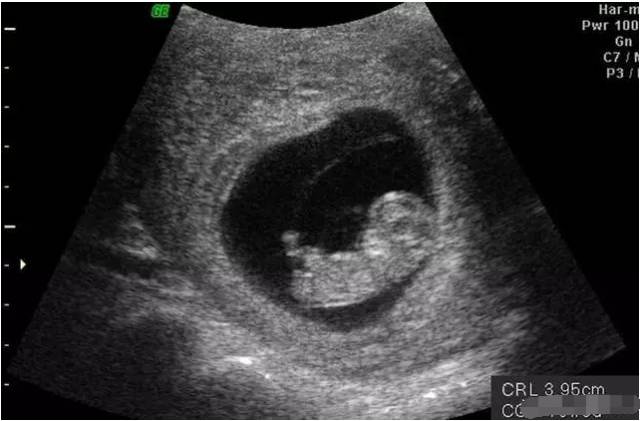

她特别痛苦,因为家人受益于无限极产品,加上听说我们外地市场的梅一丹老师和她一样的问题,就是用无限极的产品调理好了身体,抱着试试看的心理姗姗用上了无限极产品,通过老师专业的配伍,无限极产品只用对的,不选贵的 ,自己的相信和坚持,一年的时间,这个月去医院检查,结果显示她真的怀孕了。